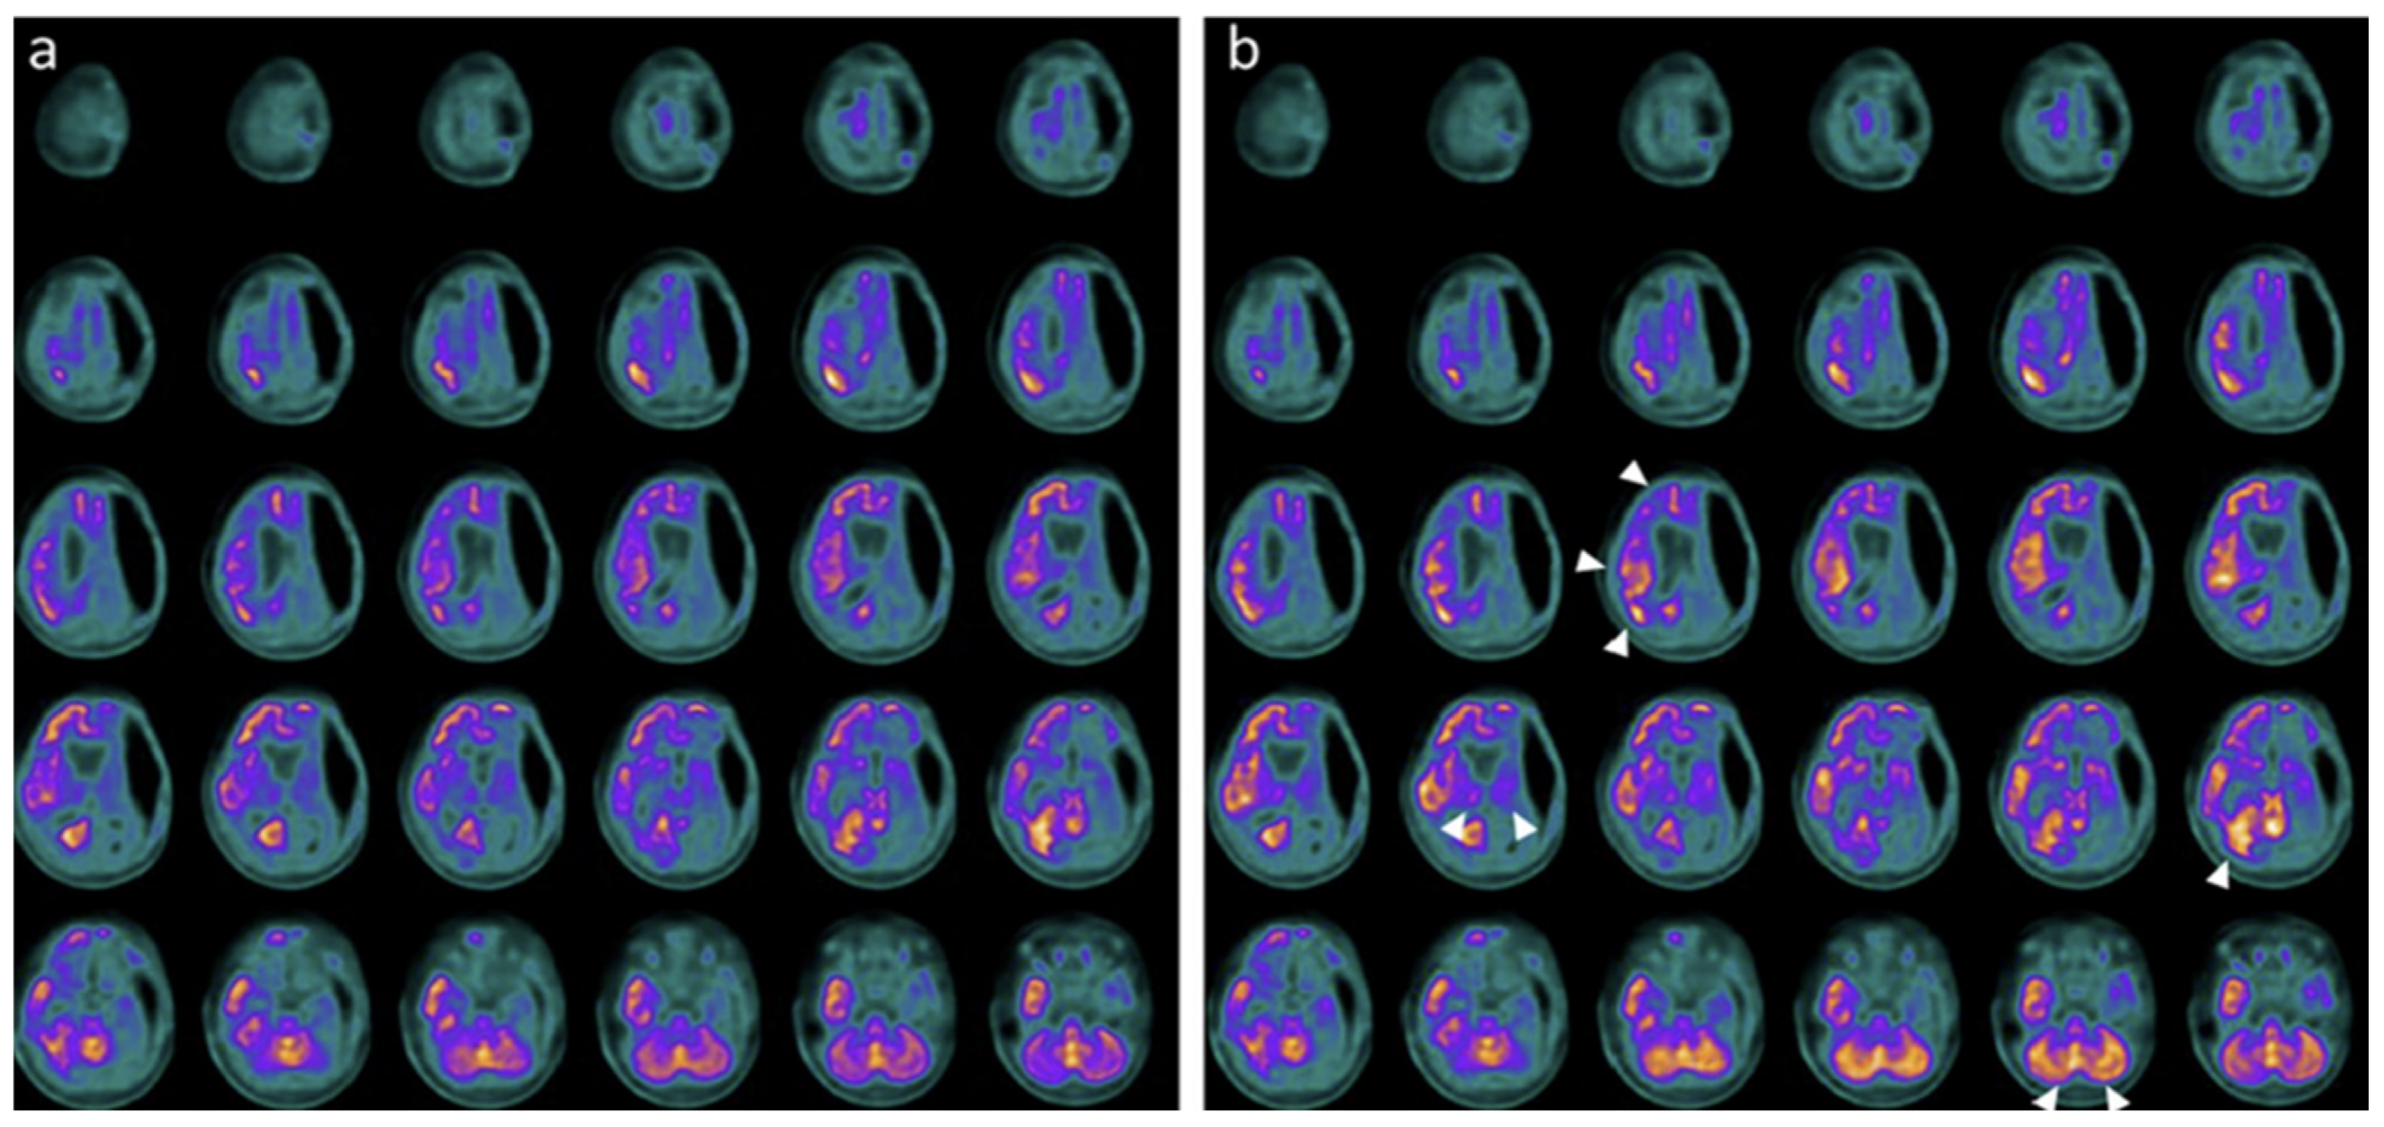

Neuroimaging and neurophysiology supported these clinical changes. Baseline PET and SPECT showed markedly reduced tracer uptake across cortical, subcortical, thalamic, and cerebellar regions, while post-treatment studies demonstrated regional metabolic and perfusion increases, particularly in the temporal, parietal, occipital cortices, thalami, and cerebellum (Figure 4, Figure 5 and Figure 6) [28].

Figure 4. PET before and after the treatment with hr-NGF in the first TBI patient. (a,b) Brain 18F-FDG PET axial slices performed before (a) and after (b) intranasal hr-NGF treatment. A mild global reduction in 18F-FDG uptake was observed in all cortical regions, whereas a more marked reduction was detected in all subcortical regions (a). After hr-NGF administration, an increase in radiotracer uptake was found in the bilateral temporal cortex (right: +7%; left: +7%), right and left thalamus (+6% and +4%, respectively), and the left caudate nucleus (+9%). The white arrows delineate the aforementioned areas. (b).

Figure 5. PET before and after the treatment with hr-NGF in the second TBI patient. (a,b) Brain 18F-FDG PET axial slices performed before (a) and after (b) hr-NGF treatment. A severe global reduction in 18F-FDG uptake was observed in all cortical and subcortical regions as well as in the cerebellum (a). After hr-NGF administration, an increase in radiotracer uptake was detected in the left and right temporal cortex (right: +18%; left: +15%), bilateral parietal cortex (right: +18%; left: +15%), right and left occipital cortex (right: +10%; left: +13%), and right and left thalamus (+7% and +8%, respectively). The white arrows delineate the aforementioned areas. (b).

Figure 6. PET before and after the treatment with hr-NGF in the third TBI patient. (a,b) Brain 18F-FDG PET axial slices performed before (a) and after (b) hr-NGF treatment. A severe reduction in 18F-FDG uptake was observed in all cortical and subcortical regions of the left hemisphere, whereas a mild reduction was detected in the whole cerebellum and all cortical and subcortical regions of the right hemisphere (a). After hr-NGF administration, an increase in radiotracer uptake was found in the right frontal cortex (+11%), right temporal cortex (+15%), right parietal cortex (+14%), right occipital cortex (+22%), right and left thalamus (+10% and +7%, respectively), and cerebellum (+33%). The white arrows delineate the aforementioned areas. (b).